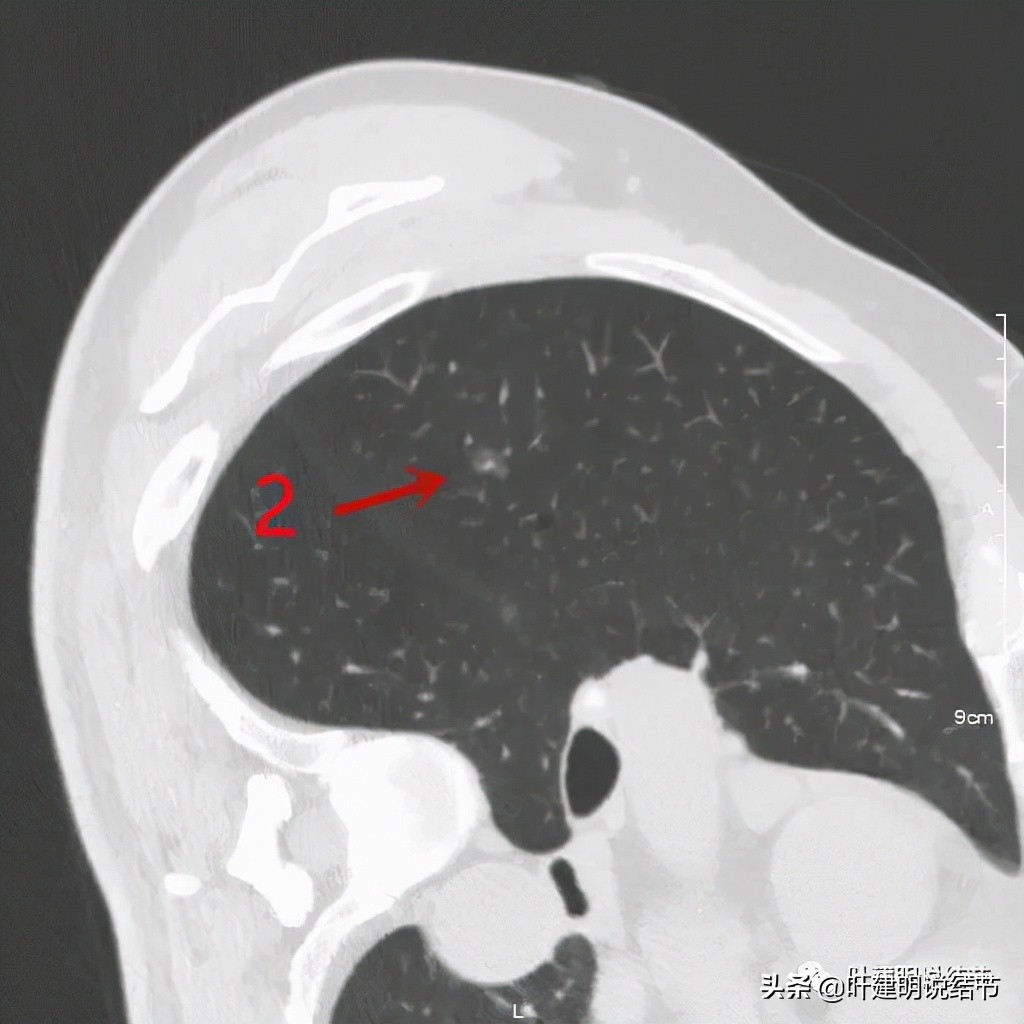

右侧病灶2:磨玻璃结节伴血管穿行,考虑不典型增生或原位癌可能性大